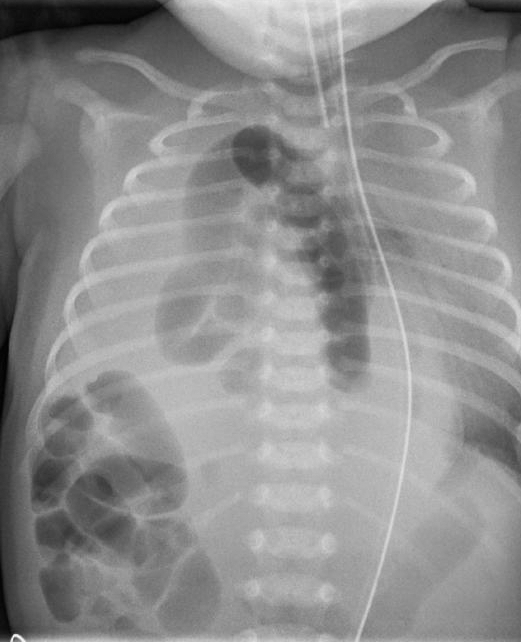

Chest radiograph (CXR) is recommended as the first diagnostic study to confirm the presence of bowel in the thoracic cavity. Figure 4 shows a CXR indicating a congenital right-sided diaphragmatic hernia in a neonate. Computed tomography (CT) can confirm the diagnosis and further delineate the severity of the CDH. Alternate studies to confirm the diagnosis of CDH include a CXR after the passage of a nasogastric tube or an upper gastrointestinal series. Management of severe CDH often includes immediate intubation, intensive pharmacological treatment, and even extracorporeal membrane oxygenation. If the patient has late-presenting CDH with mild symptoms, emergent surgical consultation still is the appropriate treatment.

Figure 4. Chest Radiograph of a Congenital Diaphragmatic Hernia |

Kinderradiologie Olgahospital Klinikum Stuttgart. ZwH kl. Wikimedia Commons. Pubilshed Dec. 2, 2014. https://commons.wikimedia.org/wiki/File:ZwH_kl.jpeg. CC BY-SA 4.0. |